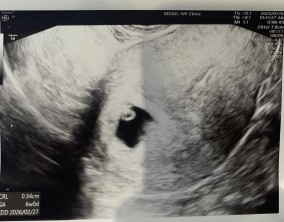

조심스러운 기쁨이 안도가 되기까지

이유정 원장님께서 차분하고 사실적으로 치료 과정과 정보를 설명해 주셔서 불안한 마음이 많이 줄어들었습니다. 미디어에서 접했던 이야기들로 걱정이 컸던 만큼, 현실적인 설명…